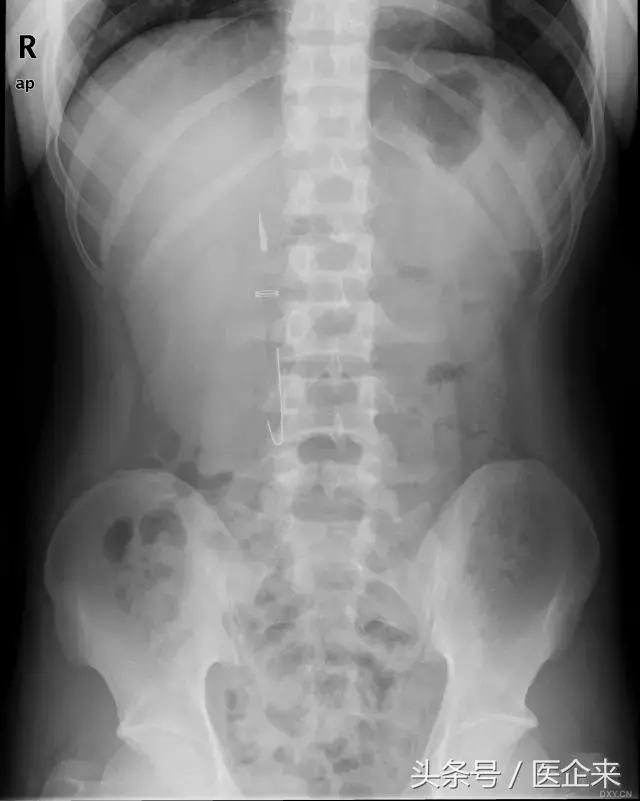

10. 经口吞入大量钉子(一句话,正常人干不出这事...)